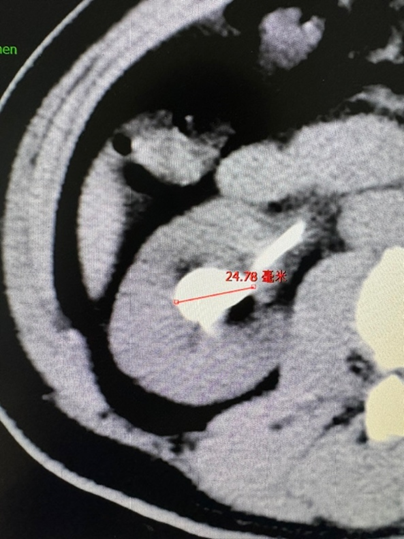

术前CT检查